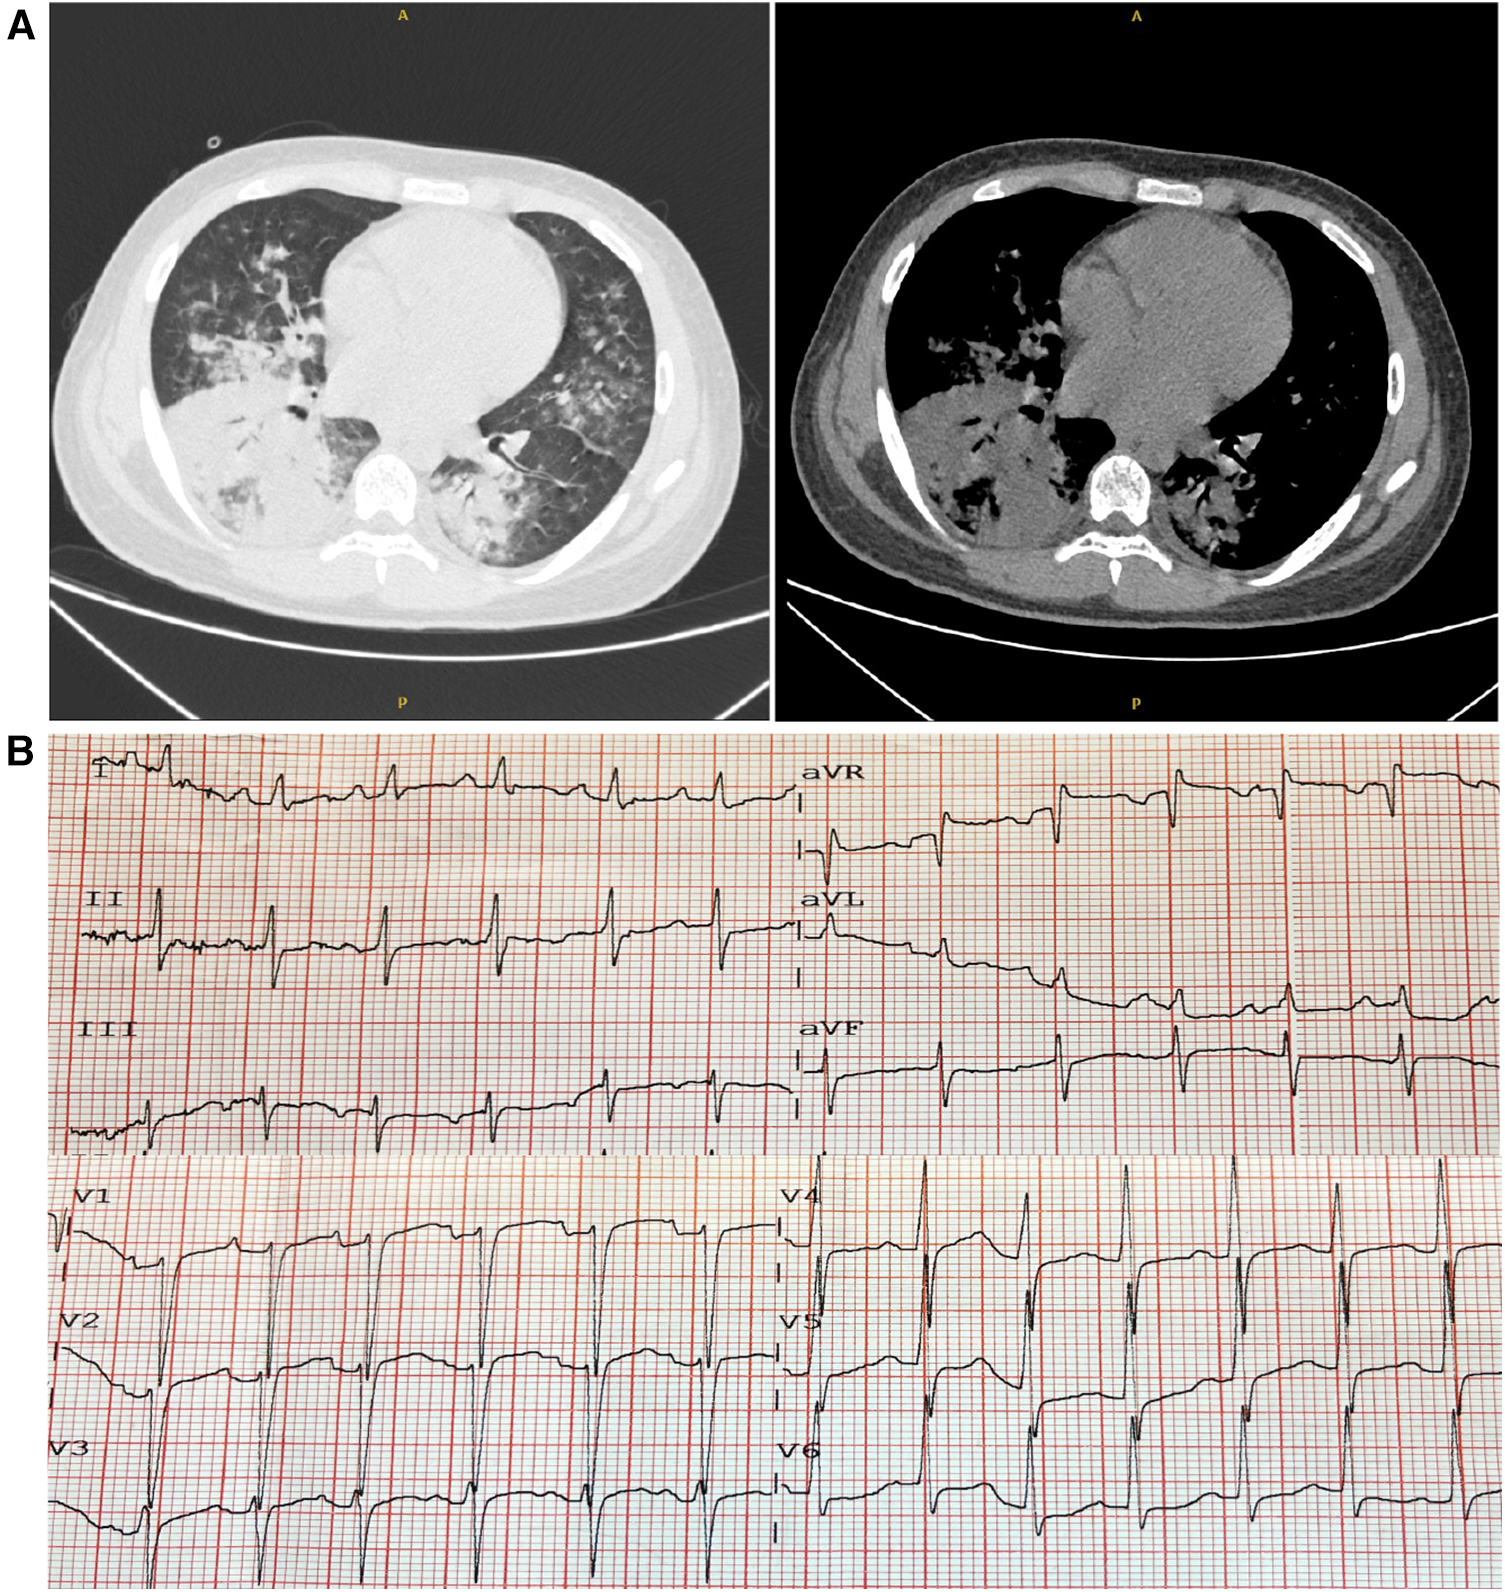

On arrival at the ER, his vitals included a temperature of 39.5°C, heart rate of 153 beats per minute, respiratory rate of 35 breaths per minute, oxygen saturation (SpO2) of 90% on room air, and blood pressure of 97/63 mmHg. His weight was 60 kg, and his height was 175 cm. The chest computed tomography (CT) scan images on admission indicated consolidation of the right lower lobe and patchy infiltrates at the left lower lobe (Figure 1A), and the ECG showed sinus tachycardia and ST-T changes (Figure 1B). In addition, echocardiography revealed poor left ventricular systolic function with global hypokinesia [ejection fraction (EF) 30%]. Laboratory findings showed an elevated troponin-T and natriuretic peptide (BNP). He was diagnosed with CAP and acute myocarditis, receiving supportive care. Alongside, piperacillin/tazobactam, as empirical antibiotics, and 40 mg methylprednisolone were administered. The next day, he was transferred to the intensive care unit (ICU) for further support.

Figure 1

Chest computed tomography (CT) and electrocardiogram (ECG) on admission. (A) The chest CT scans revealed consolidation and patchy infiltrates within the right lower lobe and the left lower lobe. (B) The ECG showed sinus tachycardia accompanied by ST-T alterations.